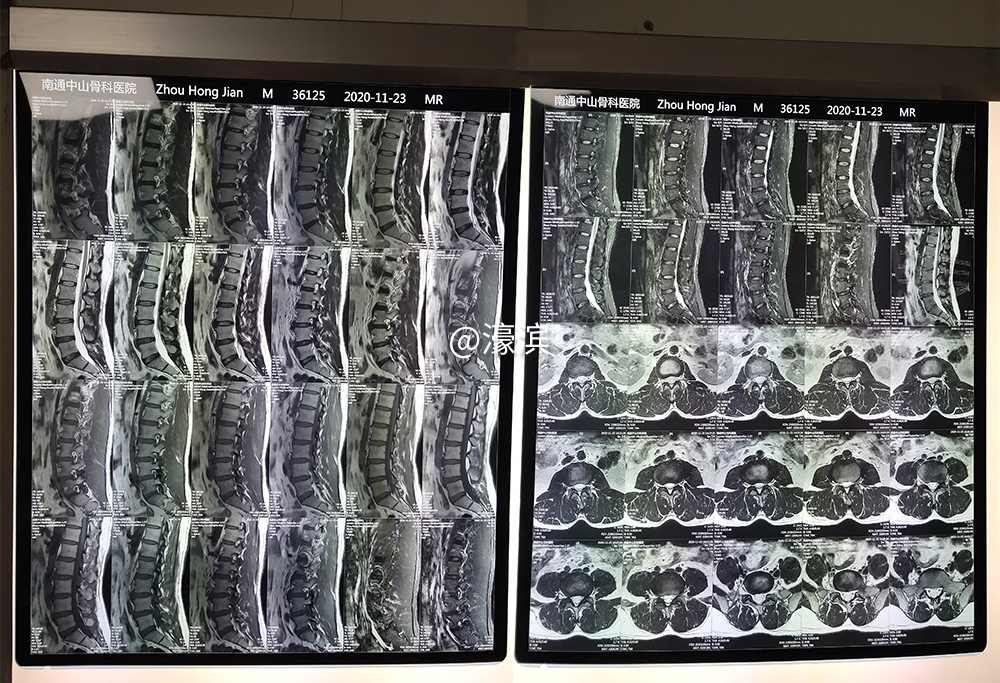

▲术前核磁检查

% X5 t& X2 l+ i; O% I; @# H  两个多月后,周先生腰臀部疼痛加重,于是在家属陪伴下前来我院就诊,经检查确诊患者实为腰椎间盘突出症,而其臀部疼痛是由于腰椎间盘突出压迫神经导致。由于周先生同时患有左股骨颈骨内软骨瘤、右髋关节炎、糖尿病等症,且腰臀部疼痛已严重影响到患者的日常生活,我院疼痛科黄正乾主任当机立断,在征得患者及家属的同意下,于入院第二日为周先生实施椎间盘射频消融术。术后第二日周先生右腿活动自如且无痛感,术后第三日周先生恢复良好,在检查无误后办理出院。四天时间,周先生的病痛得到了迅速有效的治疗,出院时,周先生及家属握着黄主任的手连连道谢。